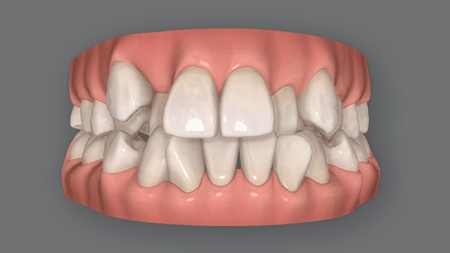

(1) 前歯斜めになってしまった

下の前歯が斜めに傾き

外側に押し出されて受け口

前歯を舌で押す癖がある人や、子供の頃に指しゃぶりの癖があった人は、下の前歯が徐々に外側に傾いて受け口になってしまいがち。

また奥歯が斜めに生えている場合、その奥歯の傾きが徐々にひどくなって前歯を外側に押し出してしまい、さらにひどい受け口になることも少なくありません。

しかも下の前歯が外側に押し出されると、それに伴って奥歯移動してしまうため、多くの場合、奥歯の噛み合わせもおかしくなっています。